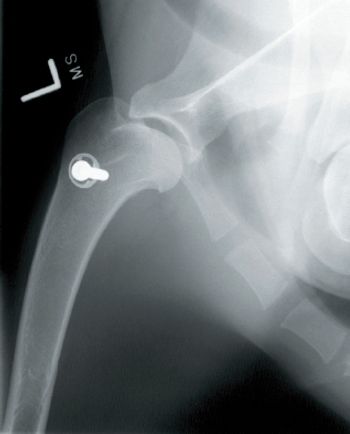

In this photo gallery, veterinary surgeon Scott Palmer demonstrates how he straightened and lengthened a disfigured leg of a Great Dane puppy by using a novel surgical technique.

Fort Collins, Colo. - To save a dog's leg, a veterinary orthopedic surgeon tried something radical.